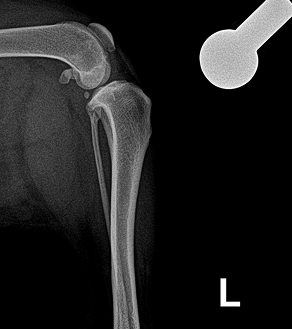

< 정상적인 십자인대 >

< 손상된 십자인대 >